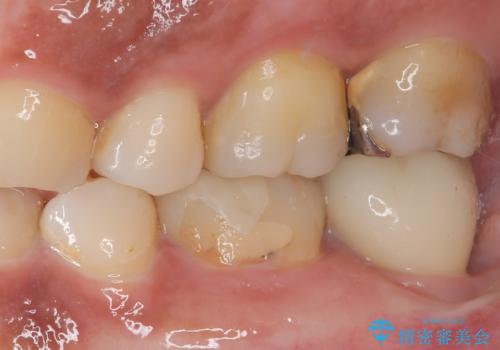

そこで今回は、抜歯即時インプラントの適応と判断しました。

抜歯と同時にインプラントを埋入し、さらにその日のうちに仮歯を装着することで、見た目と機能を即日に回復しています。